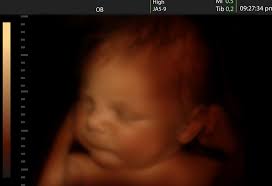

Do Babies Cry In The Womb Causes Signs Importance

Babies Cry In The Womb And 18 Other Surprising Facts I Learned When I Became A Dad The Independent The Independent

Do Babies Cry Within The Womb